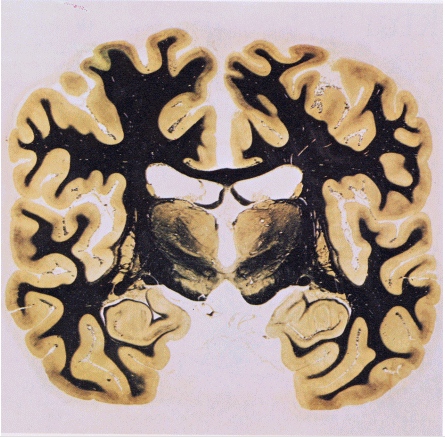

Schneidet man das Gehirn im Bereich der Ohren senkrecht auf, dann ergeben sich die folgenden Schnittbilder; auch hier erkennt man beide Male sehr schön oben unter dem Scheitel einen tiefen Einschnitt, der die beiden Hemisphären voneinander trennt; weiter unten im Schädel ist dann wieder jenes 'Breitbandkabel', der corpus callosum, zu erkennten:

Die beiden Präparate wurden mit einem Farbstoff behandelt, der die Myelinhüllen der Nervenfasern schwärzt. Die aus Nervenfasern bestehende weiße Substanz erscheint deshalb schwarz. Die vorwiegend aus Zellkörpern gebildete graue Substanz der Gehirnrinde bleiben ungefärbt. Die leeren Gebiete im Innern zeigen die Lage der flüssigkeitsgefüllten Gehirnkammern.